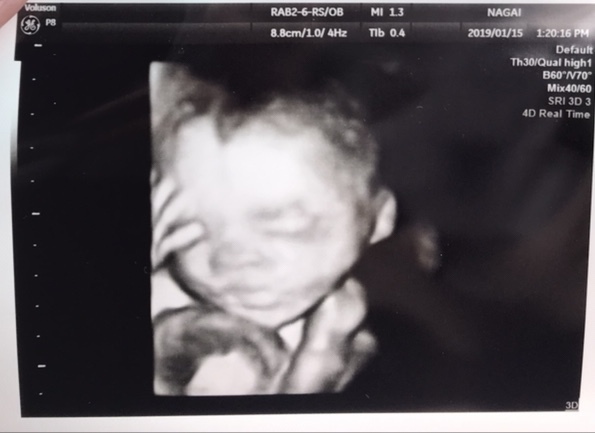

24週5日(24w5d・男の子)|ma330na さん(27歳)

エコー写真撮影時のエピソード:

今まで撮ったエコー写真の中で一番ハッキリと顔が写った写真。鼻が高めで、パパ似かなって家族で話しました。口元に手があるのもまたカワイイ。

じいじ、ばあばに見せたら、あまりにもハッキリ写ったから驚いていたと同時にとても喜んでくれました。